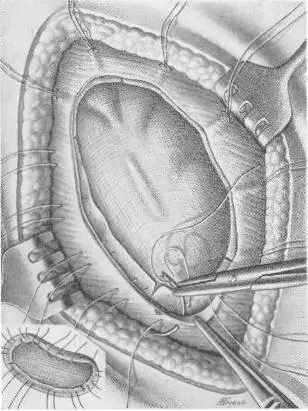

Объективно: больной — тучный мужчина, высокого роста, вес 102 кг. Послеоперационный рубец длиной 20 см. Грыжевое выпячивание размером 20 Xl5 Xl см, вправляется с трудом. На рентгеноскопии в грыжевом мешке обнаружены петли тонкой и сигмовидной кишок. Операция под эфирно-кислородным наркозом. Из рубцово-измененных тканей с трудом выделены края грыжевого дефекта (16x10 см). Петля тонкой кишки сращена со стенкой грыжевого мешка. Спайки разделены. Грыжевой мешок ушит (рис. 107 а). Произведена пластика путем подшивания двух листков капроновой сетки к краям дефекта передней брюшной стенки (рис. 107, б, в, г) [32]. Над верхним листком капрона зашита подкожная клетчатка. Рана зажила первичным натяжением, однако к 20-му дню на месте небольшой серомы образовался инфильтрат и усилилось выделение серозной жидкости из углов раны. Спустя 6 недель после операции больной был выписан для амбулаторного лечения. Через месяц поступил повторно по поводу продолжающегося выделения серозно-слизистой жидкости. Лишь спустя 4 месяца после операции отделяемое прекратилось после повторного извлечения нитей капрона из образовавшихся свищей. Рецидива грыжи нет. Закрытие прочное.

Рис. 107 а. Операция по поводу большой послеоперационной грыжи с закрытием дефекта двойной капроновой сеткой. Первый этап: ушивание грыжевого мешка, шов на брюшину.

Рис. 107 б. Операция по поводу большой послеоперационной грыжи с закрытием дефекта двойной капроновой сеткой. Второй этап: укрепление первой капроновой сетки.